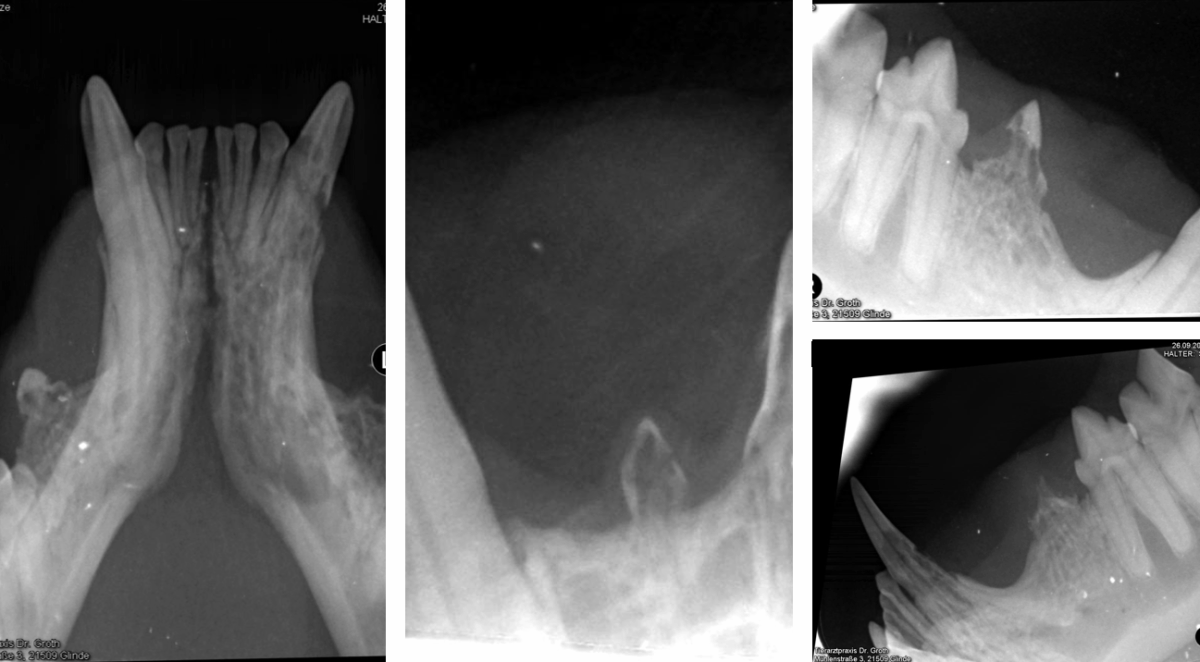

Bei Katzen kommt es mitunter zu einer chronischen Entzündung der Zahnwurzeln aller Zähne. Hier liegt eine autoimmunbedingte Krankheit zugrunde, die sich FORL (Feline Odontoclastic Resorptive Lesions) nennt. Katzen leiden dabei unter starken Zahnschmerzen, es sind hochgradige Veränderungen von Zahnfleisch und Zahnapparat zu erkennen.

Nach ausführlicher, röntgengestützter Diagnostik (Dentalröntgen), findet eine Extraktion der betroffenen Zähne statt.